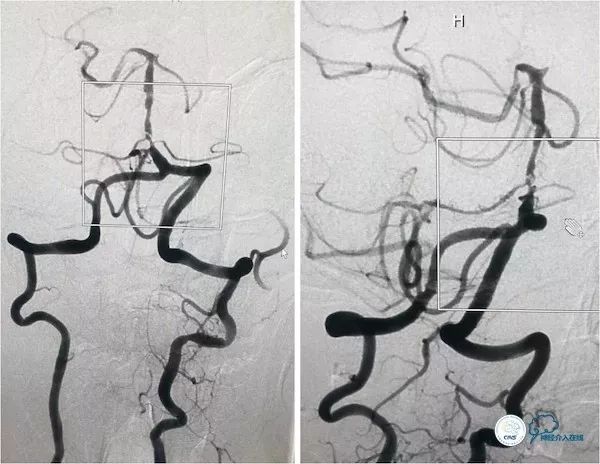

行头颅DSA示左椎动脉优势,左椎动脉V2段迂曲,基底动脉下段重度狭窄;左颈动脉造影见左后交通动脉开放,向双侧大脑后动脉及基底动脉远段代偿(2016-4-11,图3、4、5)。

图3

图4

图5